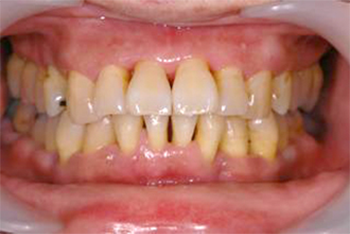

上の写真のように歯と歯の隙間が広くなったり、歯があらぬ方向に動き出し、出っ歯になったりもします。

歯を失うという事は、歯の周りの骨が大きく喪失し、顔の表情にも大きな変化をもたらします(写真下)。